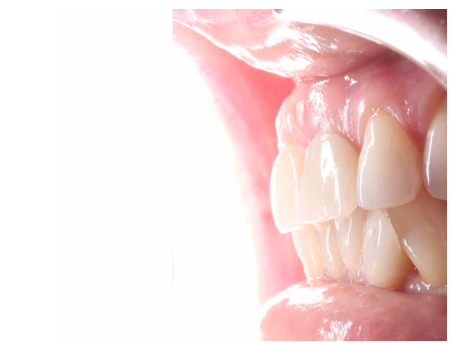

A los 6 meses se puede observar una correcta disposición de los tejidos blandos, así como la estabilidad de estos en el tiempo debido al manejo de los mismos a través de la prótesis provisional (Figura 24). Se realizó además un control radiológico para conocer el estado de los tejidos duros (Figura 25).

Dada la correcta evolución del caso a los 6 meses, se llevó a cabo el registro de la posición del IOI y del perfil de emergencia mediante un transfer individualizado con el fin de replicar de forma fiel y detallada la arquitectura gingival (Figuras 26 y 27). Finalmente se colocó la prótesis fija final atornillada al IOI a los 7 meses del inicio del tratamiento (Figuras 28 y 29).